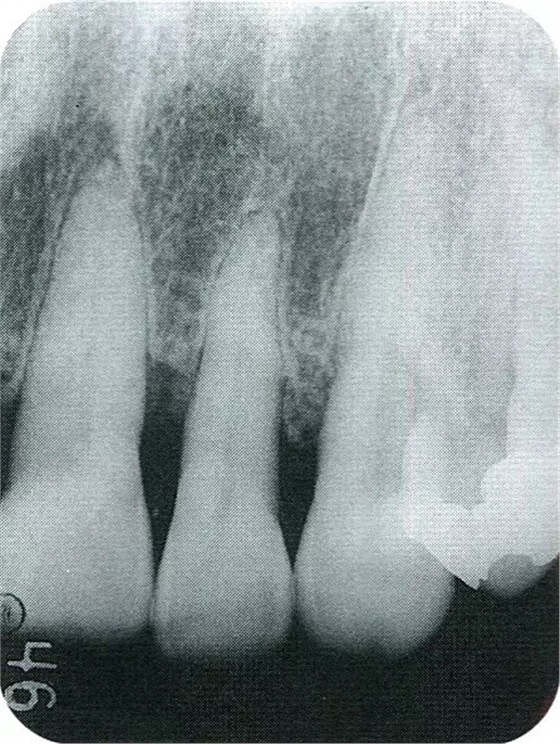

▲圖7-7術(shù)前,術(shù)后的x片。確認(rèn)出現(xiàn)骨再生,牙槽嵴硬線。